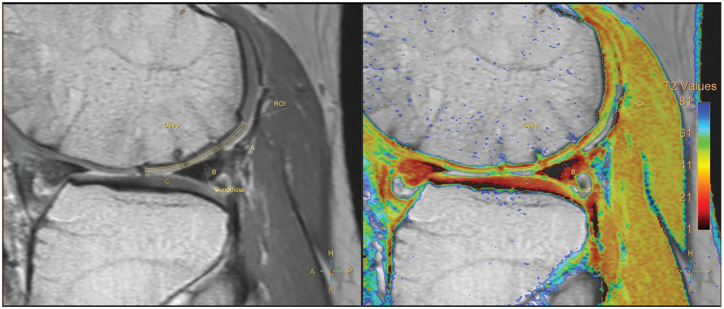

Methods: Patients who underwent AOT between 2002 and 2021 and were followed for a minimum of 2 years were retrospectively reviewed. Clinical outcomes were assessed at postoperative early term (1-2 years postoperatively) and at the short- to midterm period (2-6 years postoperatively) using the Lysholm score, International Knee Documentation Committee (IKDC) score, Tegner activity scale, and visual analog scale (VAS) for pain. Morphology of cartilage was evaluated using MOCART (magnetic resonance observation of cartilage repair tissue) 2.0 scores, and quality was assessed using quantitative magnetic resonance imaging (MRI) T2 mapping. In those who were assessed with serial MRIs at early term and short-to-midterm intervals, correlation analysis was performed to assess the relationship between MRI and clinical outcomes.

Results: A total of 45 patients with a mean age of 36.6±14.0 years (range, 16-63 years) were included. The mean follow-up period was 4.3±1.2 years. The mean MOCART score was 84.0±11.5 at early term and 78.1±21.0 at midterm, with no significant changes between follow-up intervals. T2 value also remained unchanged between postoperative follow-ups. Significant improvements in the Lysholm, IKDC, and VAS scores observed at the early term improved further through the midterm period. The MOCART score at the postoperative early term was correlated with VAS improvement (P = .003); however, no significant correlation was found between other clinical and MRI outcomes.